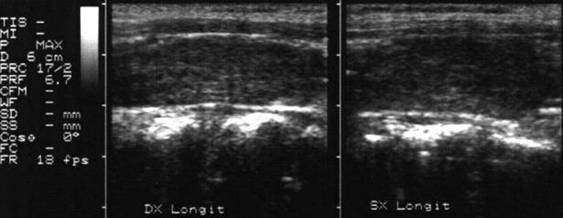

Carcinom ANAlaZic.Recidiva laterocervicalA

Femeie de 73 ani. Recidiva laterocervicala dreapta

dupa meta de carcinom anaplazic.

Prima imagine este efetuata la 3 luni dupa interventia chirurgicala si evidentiaza

o leziune de 20x23x24mm (5,7 cc).

A doua imagine s-a efectuat la 25 de zile dupa prima; leziunea masoara 33x42x40mm,

(29 cc).

Examen citologic: carcinom anaplazic.

Aceeasi pacienta - vascularizatie slaba la doppler datorata necrozei.